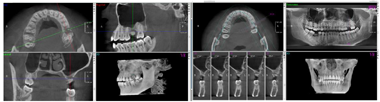

术前CT检查(图3)。

术中操作详见图4。术后6个月复查结果详见图5、图6。患者戴牙CT、种植前后CT对比图及戴牙1年后复查CT结果详见图7,图8,图9。